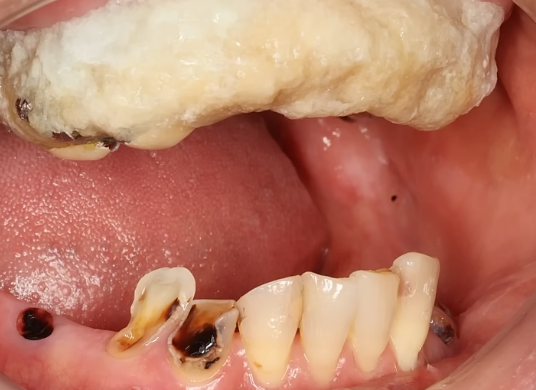

自作の入れ歯

40代患者

30年間歯医者行かずにこのザマw

白い塊はセメダインw